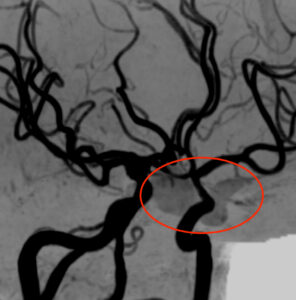

さらに、MRA検査で脳血管を見てみました。

下垂体部分に血流を示す信号を認め、下垂体卒中3)と診断しました。